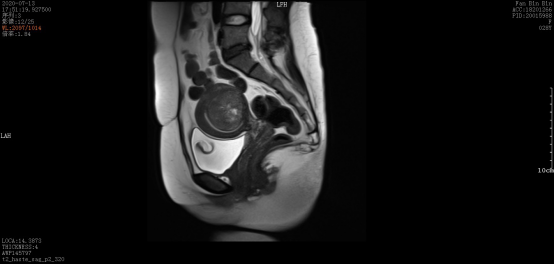

术后:

微波消融后肌瘤病灶内会发生凝固性坏死,即刻超声造影就可以看到病灶内没有造影剂充填。磁共振增强扫描病灶内呈现充盈缺损,增强后呈黑色区域,表示病灶坏死区域。坏死的病灶随时间推移,会逐渐萎缩吸收,子宫体积也会有一定的缩小,从而使痛经、月经量多等临床症状得到缓解和改善。